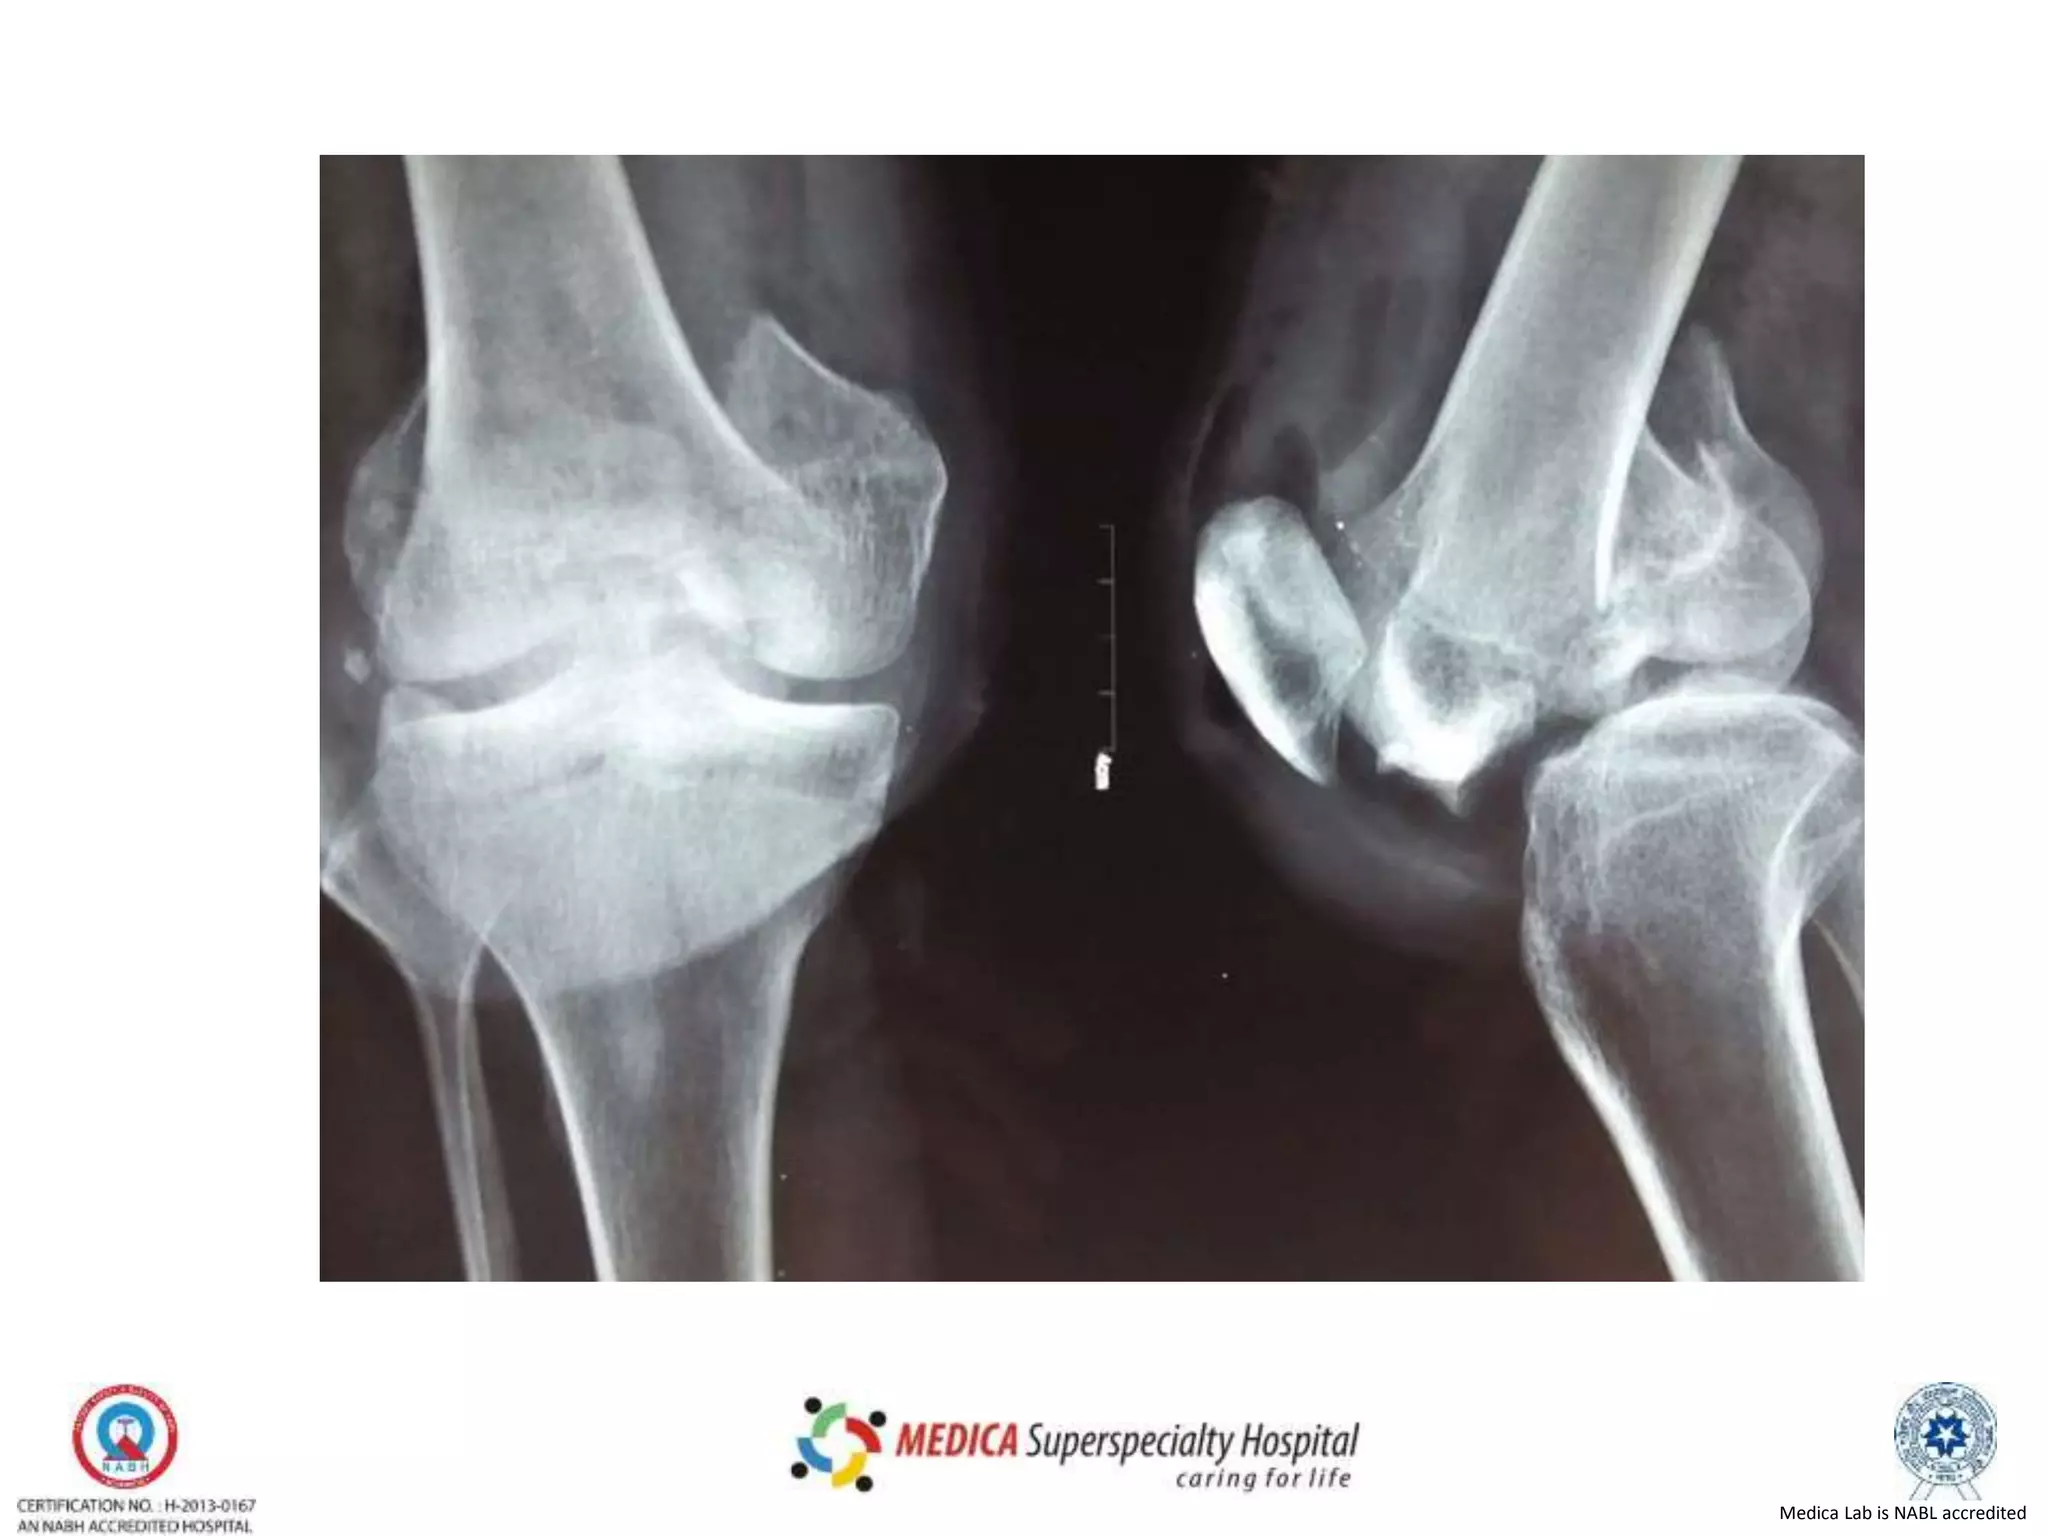

X Rays

• On AP Fore shortened Fracture condyle may lead to

appearance of varus or valgus mal-alignment.

• On true lat the femoral condyles are not

superimposed.

• Be wary to misinterpret those as poor X ray.

• Oblique view may be useful but when in doubt CT is

preferred.